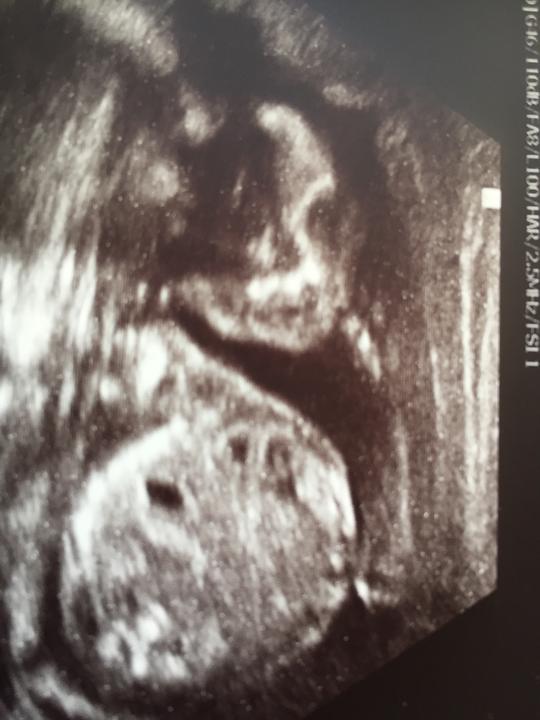

Unser Wunder <3

18 fotiek